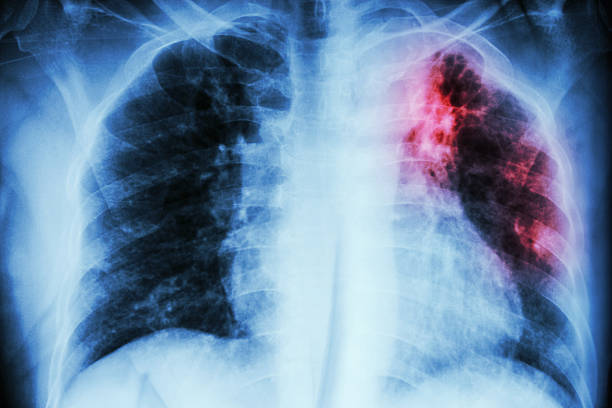

Diagnóza tuberkulózy se stanoví na základě symptomů, charakteristického nálezu na skiagramu hrudníku a průkazu mykobakterií. Je nutno zvažovat i všechna plicní onemocnění, nespecifické pneumonie, bronchogenní karcinom, sarkoidózu, plicní infarkt, silikózu, Wegenerovu granulomatózu atd.